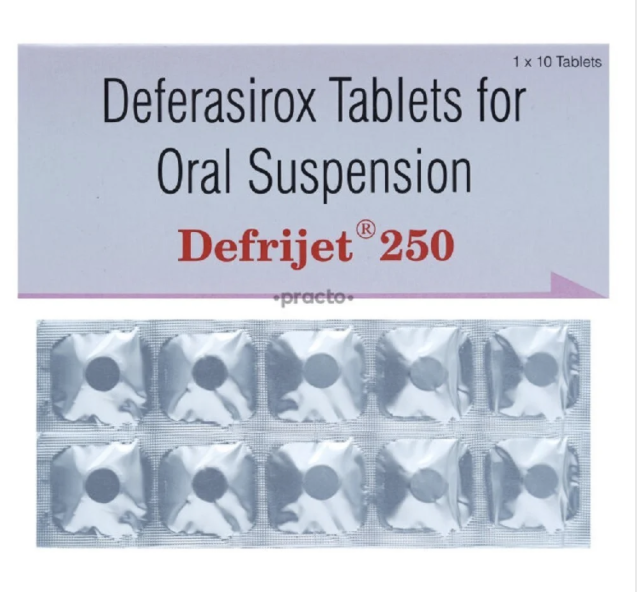

Trending products